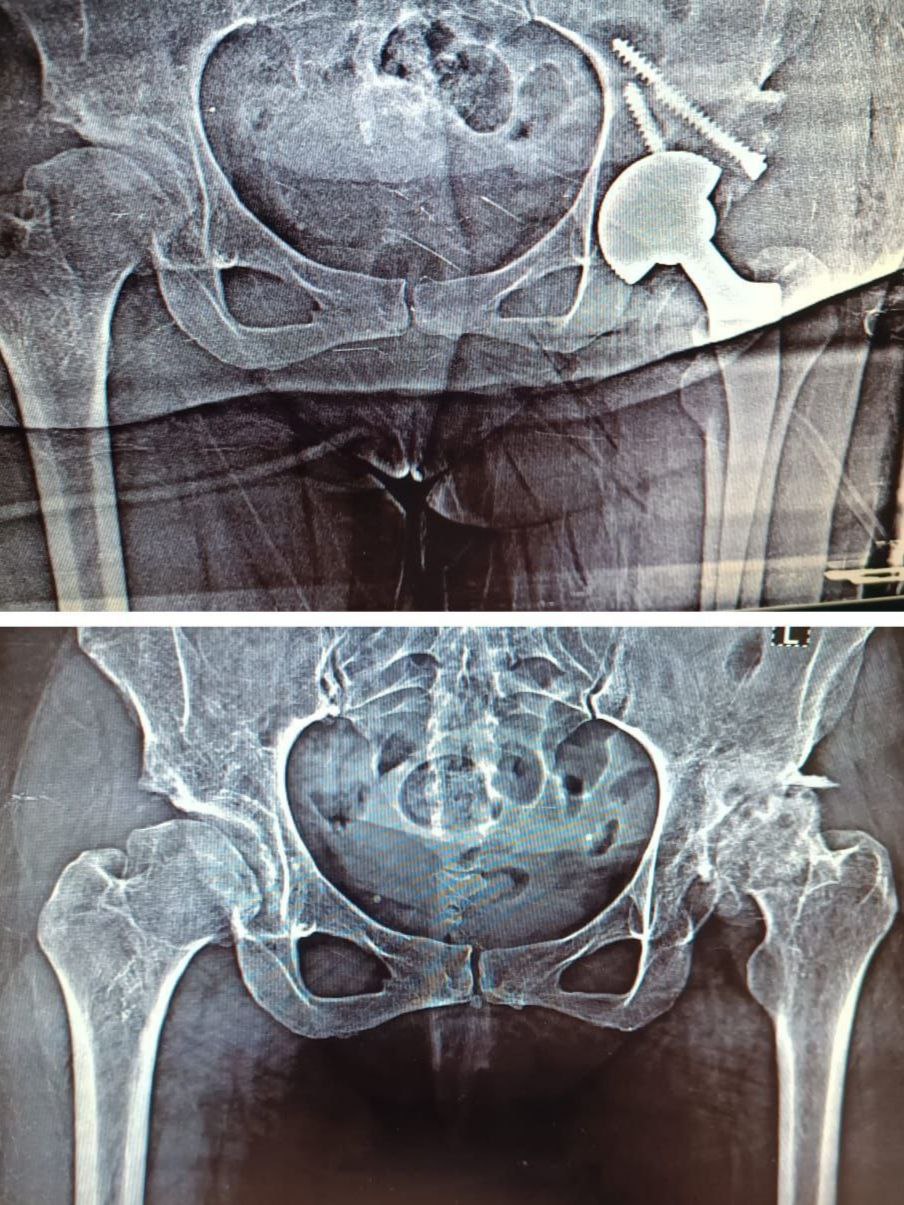

مفصل ورك أسمنتي

الصورة تُظهر نتائج عملية تبديل مفصل ورك إسمنتي حيث تم استبدال المفصل المتآكل بمفصل صناعي عالي الدقة، وتثبيته بمادة إسمنتية طبية لضمان ثبات فوري ووضع تشريحي مثالي. تم تنفيذ العملية بالتعاون بين شركتنا والدكتور [حسن السيد عمر ]، مما أظهر نتائج ممتازة من حيث المحور والاستقرار والدقة الجراحية